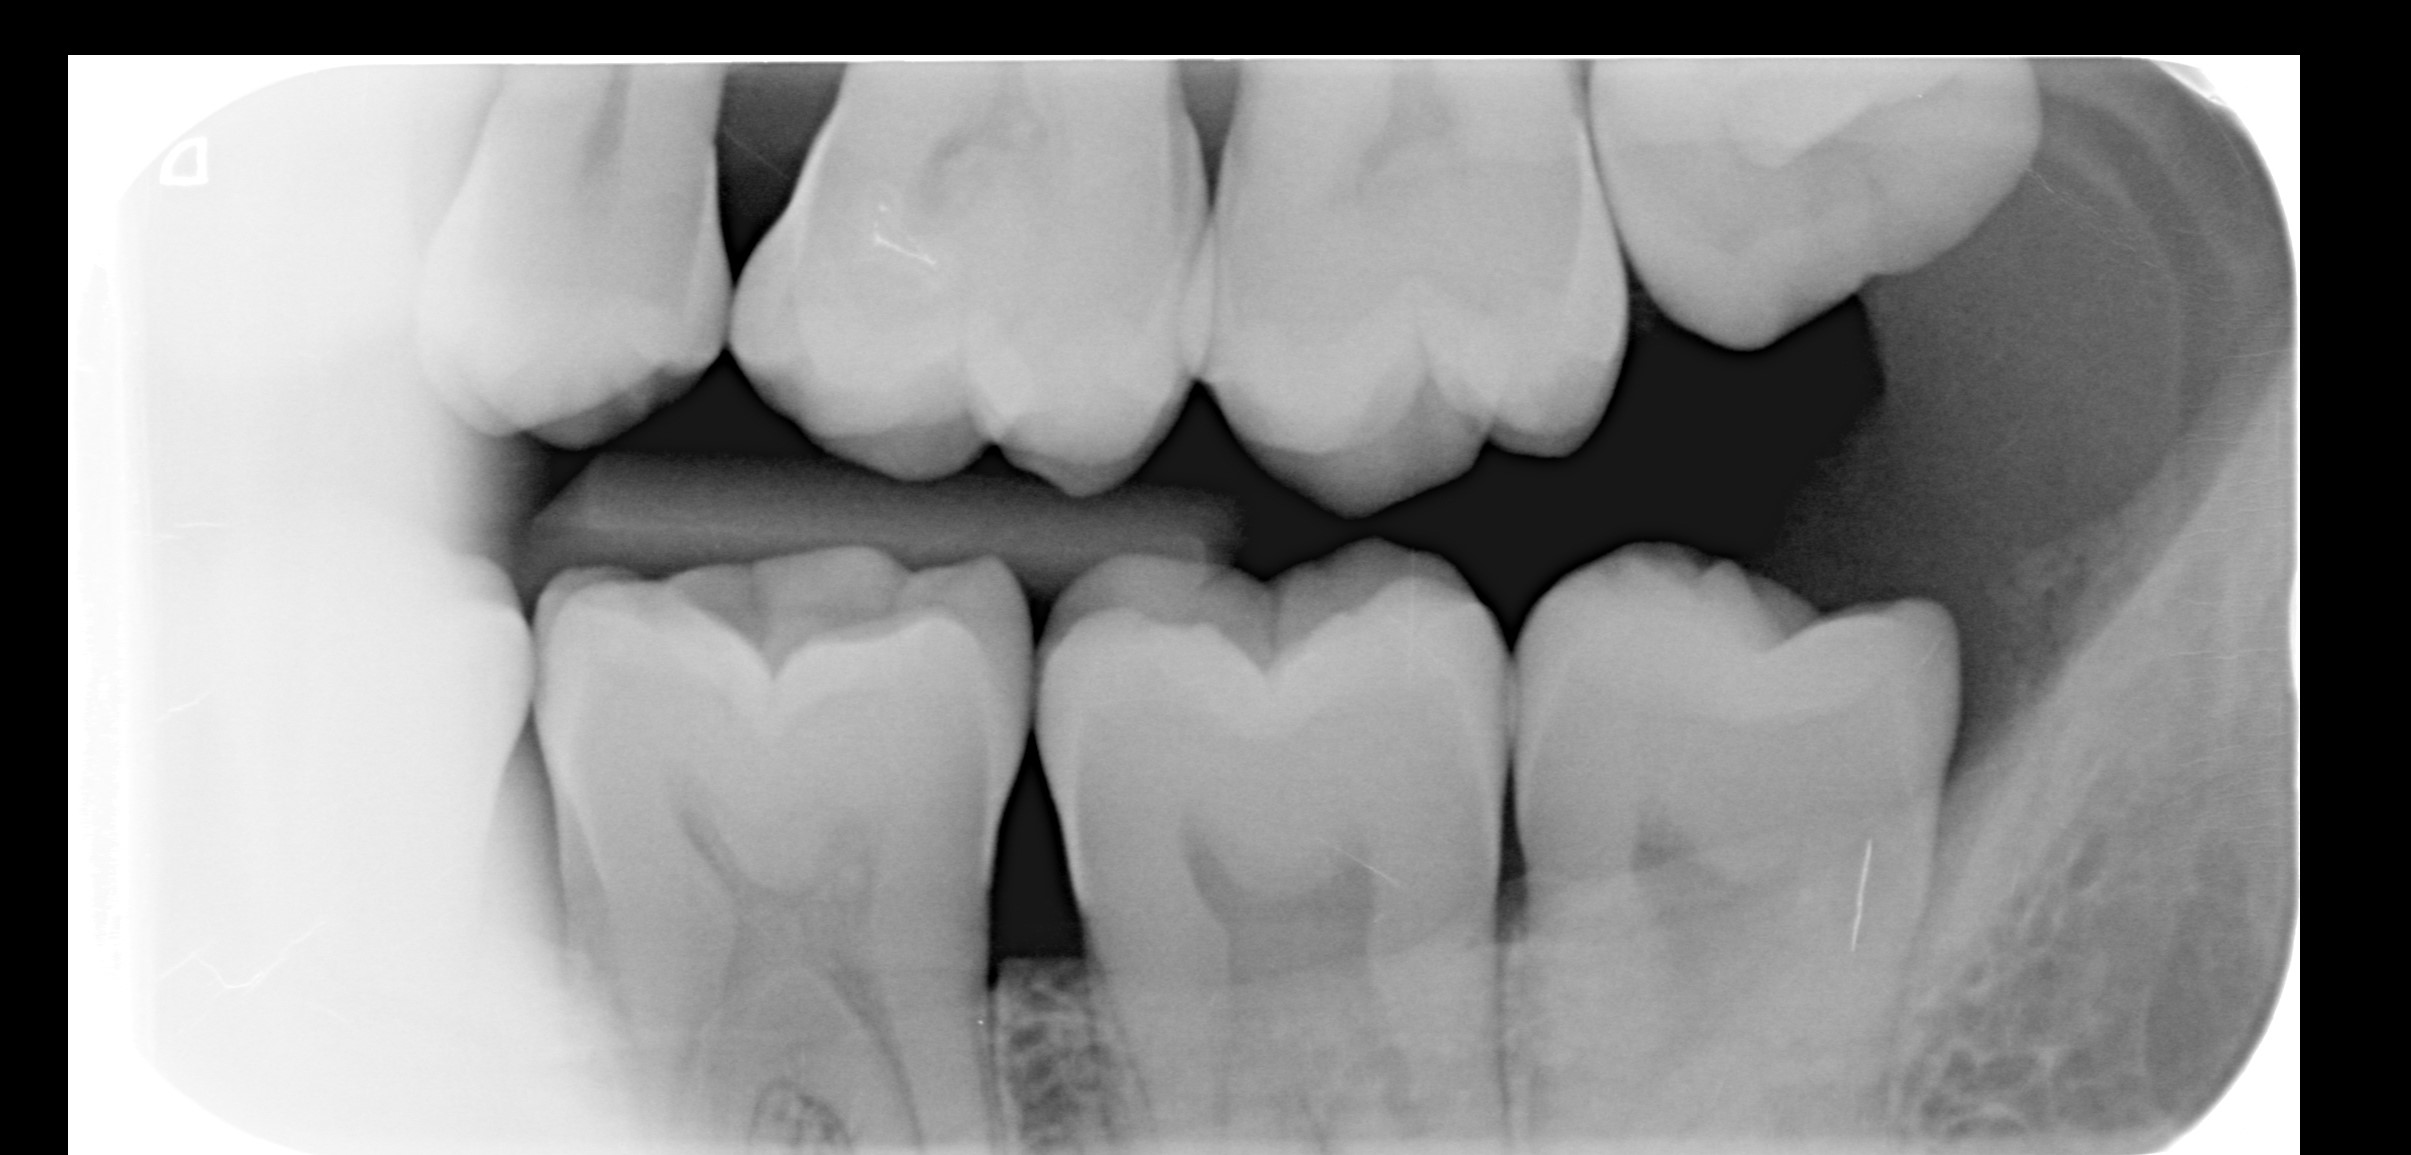

Heb al circa een week last van pericoronitis (wel vaker gehad). Deze keer duurt de genezing wat langer. Pijn is helemaal weg, maar het tandvlees daar is nog zacht en niet strak tegen de verstandskies. Foto 1 is hoe het nu is, zacht tandvlees, en foto 2 toen het gezond was waarbij het tandvlees strak is. Wanneer zal de zachtheid weggaan? Ik spoel al dagelijks met zoutwater. Ben ook van plan om in 2026 mijn verstandskiezen te verwijderen. Foto 3 en 4 zijn foto's van mijn verstandskiezen, heb alle 4 al meer dan 12 jaar niet laten trekken, maar denk dat ik het beter kan doen? Werd wel vaak gezegd tegen me dat het slim is om ze te laten trekken, maar ik ben altijd bang van zulke behandelingen.

Ik zou ze laten verwijderen... Waarom wachten op weer een irritatie. Het ziet er niet verontrustend uit...goed schoon houden. Let ook op uw drink en eet gewoonten... Flink slitage. Of ander oorzaak??. Bot trekt ook iets omlaag..Ragers gebruiken bij ieder poets beurt....hoop dat u niet rookt.